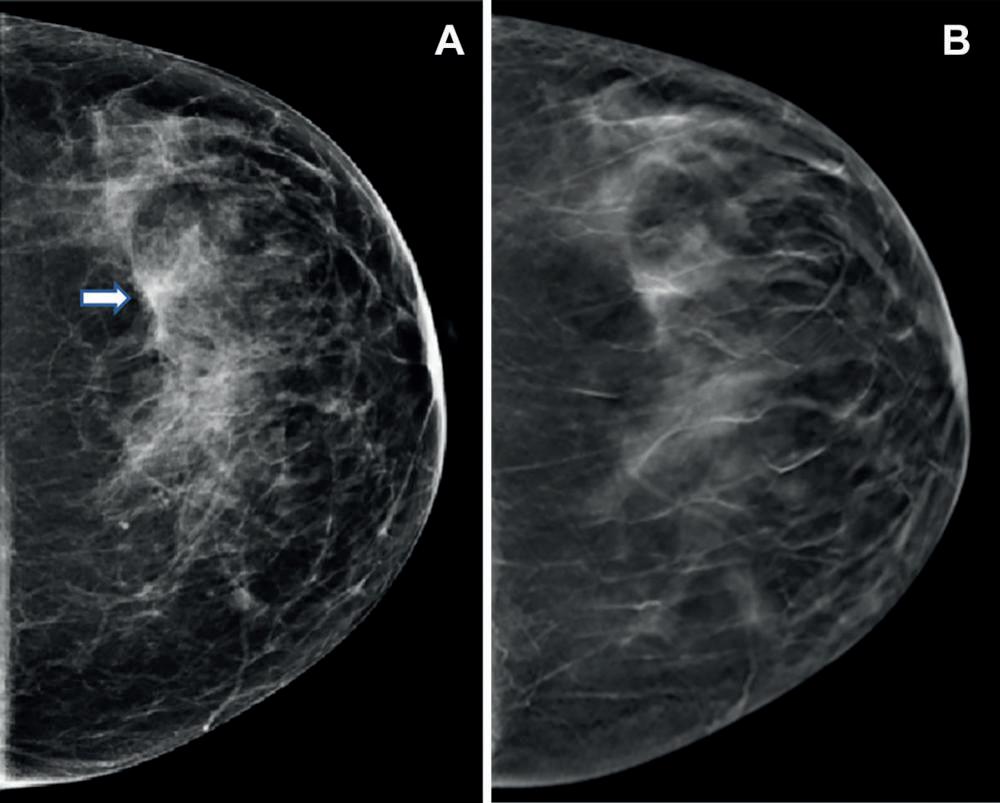

grafía digital craneocaudal bidimensional y (B) Mamografía digital mediolateral bidimensional que muestran tejido mamario heterogéneamente denso sin anomalías. (C) Imagen de tomosíntesis mamaria digital mediolateral que muestra una sutil distorsión arquitectónica (flechas) que se extiende superiormente desde el nivel del pezón. (D) La imagen ecográfica diana de la mama derecha muestra una masa irregular, hipoecoica y muy sospechosa (flecha). La biopsia central guiada por ecografía arrojó carcinoma ductal invasivo con carcinoma ductal extenso in situ (T2N0M0; receptor de estrógeno positivo, receptor de progesterona positivo y receptor del factor de crecimiento epidérmico humano 2 negativo). (MI) La resonancia magnética de la mama derecha adquirida para evaluar la extensión de la enfermedad muestra un artefacto de clip en la cara superior de la masa con realce irregular (flechas). No se observaron otras lesiones sospechosas.

Figura 1. Creación de la cohorte de estudio. El diagrama de flujo describe cada criterio de inclusión y exclusión que debe cumplirse para su inclusión en el análisis. Las mujeres con edades entre 40 y 79 años en el momento de la selección y sin antecedentes de cáncer de mama en la mamografía Figura 2. Imágenes en una mujer de 42 años que acude rutina. (A) Mamo- Dra. Emily F. Conant Por Ezequiel Domb Nota de Prensa de la RSNA

una asimetría (flecha). (B) Imagen de tomosíntesis mamaria digital craneocaudal izquierda que no muestra lesión sospechosa sino más bien una superposición de estructuras fibroglandulares y ligamentosas normales.

Figura 3. Imágenes de una mujer de 47 años que acude a cribado de rutina. (A) La mamografía digital craneocaudal muestra densidades fibroglandulares dispersas. En la vista lateral craneocaudal de la mamografía digital izquierda, se observa